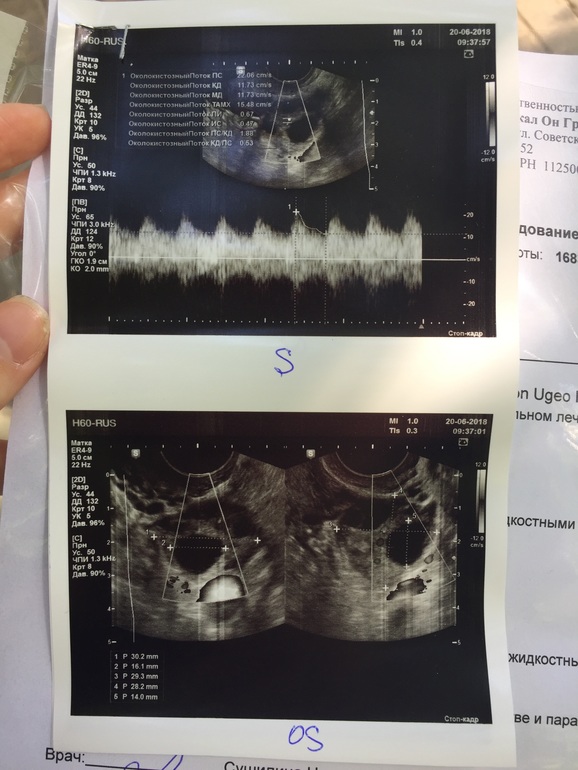

Хожу в основном в одно и тоже место, там аппарат хороший и врач.. но попала сегодня на другого врача, и она не знает!! Говорит, что О была, потому что у правого Я есть жидкость, но ЖТ не видит 😄🤷♀️ возможно типа ещё не образовалось, или не видно из-за еще одного ДФ 17мм.. или это вообще тот же фолликул, что и на 14дц был🤦🏼♀️ Та же история с ЛЯ.. но там вроде все-таки ЖТ есть, и то не факт😂

Вот теперь сижу, гадаю...) жду протокол)) по сути.. от укола 10000 фолликулы же не могли остановиться/уменьшиться.. они либо в кисту бы уже ушли, либо лопнули. Но кист нет, и нет ЖТ.. есть 2 ДФ в каждом Я. Узист даже не стала писать в заключении.